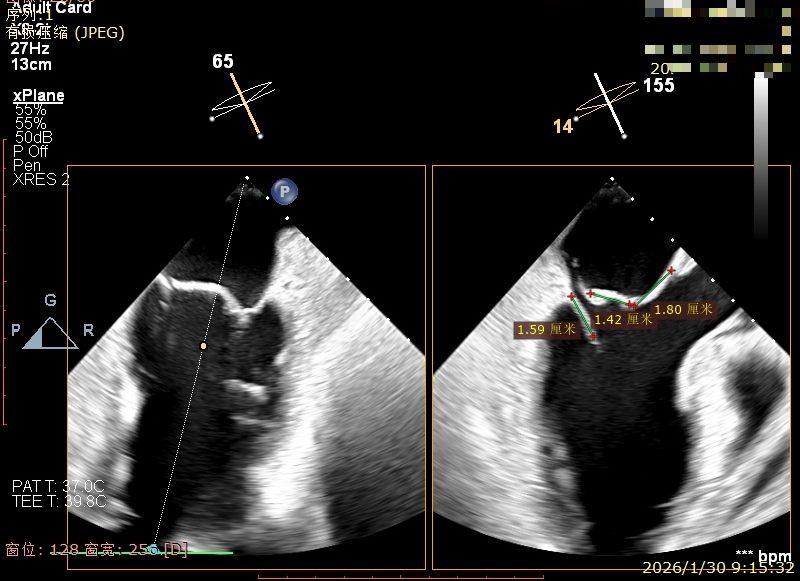

X-Plane切面切3区可见前叶脱垂

3区上Color,可见反流来源

3区前叶长度约22mm,后叶长度约11.6mm

2区前叶长度约32.2mm,后叶长度约16mm